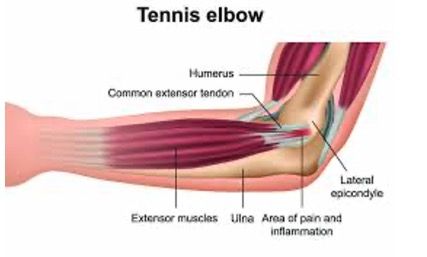

What is Tennis Elbow?

Tennis Elbow is a condition that is associated with overuse of the extensor muscles of the forearm and the tendons become inflamed where they attach to the lateral epicondyle of the elbow. Tennis Elbow is not only caused by playing tennis, but rather any activity that causes repetitive extension of the wrist: Moving the back of your hand towards the back of your forearm or rotation of the forearm can result in tennis elbow. Symptoms of Tennis Elbow include localised pain over the lateral aspect of the elbow which can radiate into the forearm and wrist. Symptoms of Tennis elbow/lateral epicondylitis generally come on gradually and progressively worsen.

Identifying the cause of tennis elbow is important. This will allow the identification of any incorrect biomechanical load that is stressing the joint and for correction of these biomechanics. This combined with adjustment of the elbow to restore correct biomechanics, the release of tight involved muscles and ice to reduce the inflammation in the area aids in the improvement of symptoms.

Golfers’ Elbow is similar to Tennis elbow however the pain and symptoms is felt on the medial epicondyle of the elbow